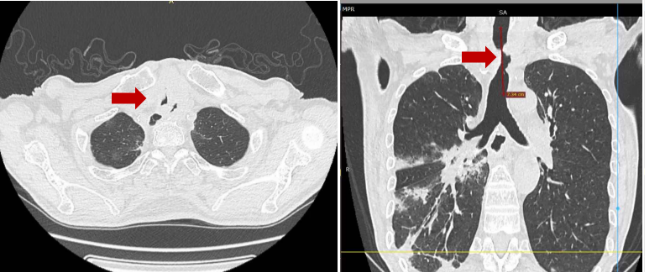

胸部CT显示气管局部肿物,大气道狭窄最严重处(红色箭头处)仅4mm

气管狭窄在颈部及胸部恶性肿瘤患者中很常见,由于恶性肿瘤生长速度快,常常侵犯气管导致复杂的气管狭窄,患者会出现较重的呼吸困难,是一种严重的临床急危重症,常会导致患者死亡。刘先生曾因食管癌进行过两次手术,影像结果显示食管癌转移到气管,导致气管管腔重度狭窄,最严重处直径仅4mm左右,狭窄段则长约3-4cm,气管镜下可见菜花样新生物的同时还伴有表面渗血、黏膜坏死,到院就诊时,已经出现了典型的“三凹征”,即吸气时胸骨上窝、锁骨上窝、肋间隙也出现了明显凹陷,提示刘先生严重呼吸困难。若不及时治疗,他随时可能因为痰堵窒息或呼吸衰竭导致生命意外。